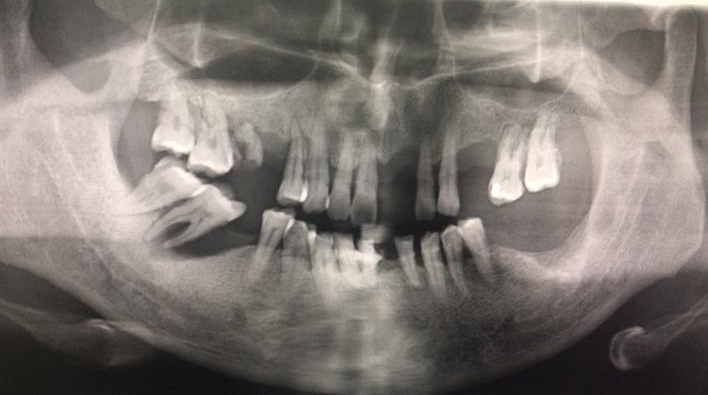

种植手术本身的难度是由患者个体的口腔状况决定的,有的患者口腔状况好,只需要植入种植体就可以了,那么收费就会相对便宜;有的患者口腔状况差,要治疗牙周炎,要植骨……如果同时要做四五个手术才能完成种植治疗,那么费用就会相对高些。